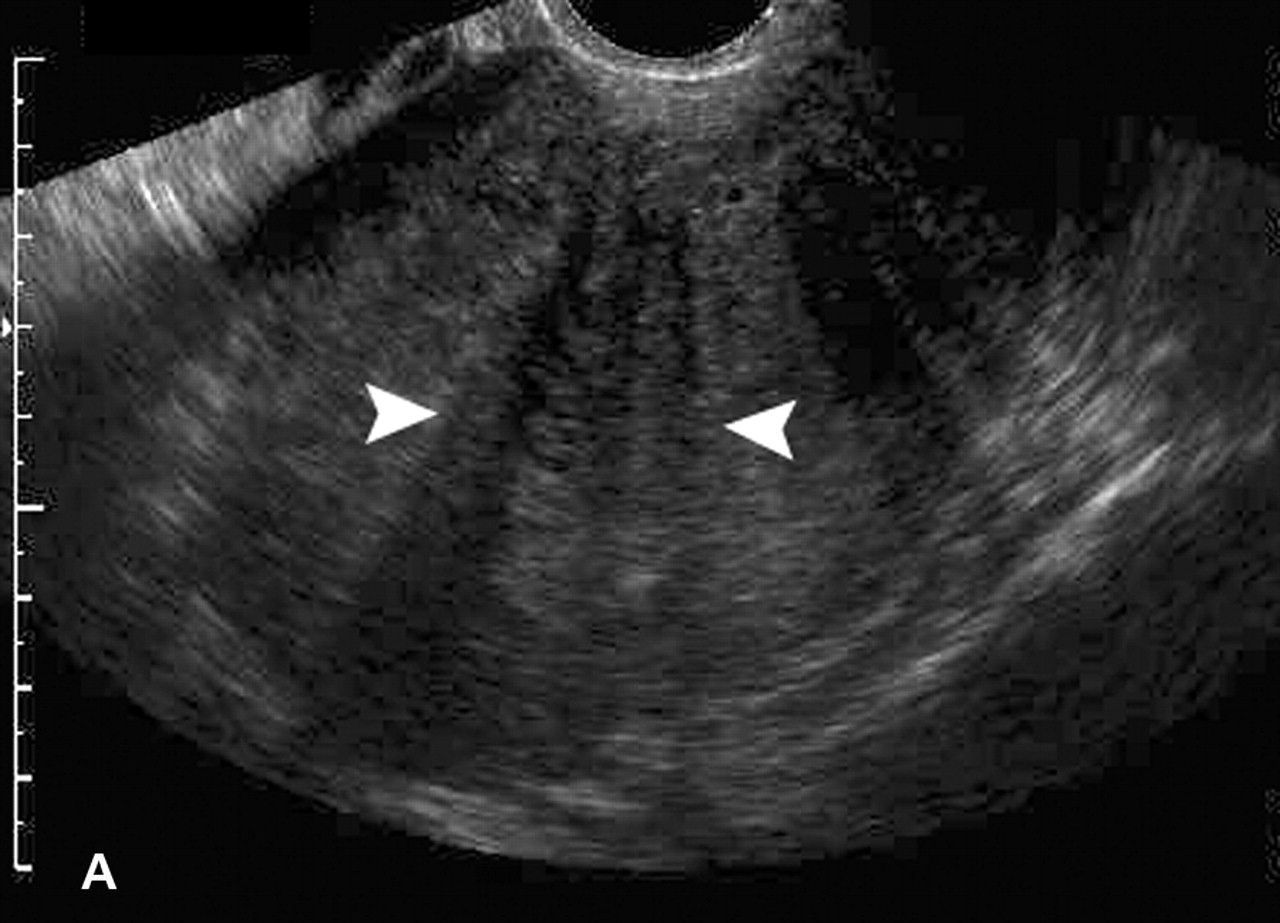

Когда дело доходит до визуализации, этим пациентам обычно назначают трансвагинальное ультразвуковое исследование, чтобы определить, есть ли причина боли в области таза, которую можно визуализировать.Поверхностные имплантаты эндометриоза нельзя увидеть ни на УЗИ, ни на каком-либо другом методе визуализации. Однако эндометриомы часто обнаруживают на УЗИ. Эндометриомы обычно выглядят как простые кисты. Однако их также можно рассматривать как множественные кисты или кистозно-солидные образования. Типичный вид этих поражений на УЗИ демонстрирует низкоуровневые однородные эхо-сигналы, иначе описываемые как внешний вид матового стекла. Это согласуется со старым геморрагическим мусором. Эти поражения также обычно лишены какой-либо васкулярности при исследовании с использованием допплеровского потока.[35] [36]

Если опухоль придатков присутствует и известна из изображений, есть характеристики массы, которые могут указать, что это за образование придатков.Эндометриомы, как обсуждалось в разделе оценки выше, имеют характерный вид матового стекла на УЗИ. Эти результаты также наблюдаются при геморрагических кистах, и часто диагноз между ними не устанавливается до момента операции. Поэтому, имея дело с визуализацией эндометриом, важно учитывать геморрагические кисты при дифференциальном диагнозе. [52]